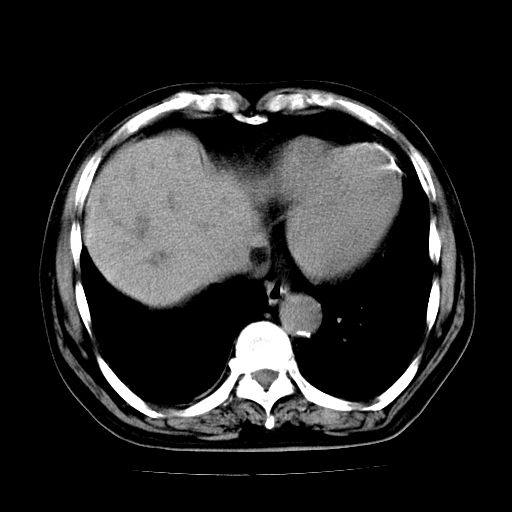

标题: CT25226:男,71岁,皮肤黄染四天。 [打印本页]

男,71岁,皮肤黄染四天。

肝内外胆管及胆总管上段扩张,考虑为梗阻所致,建议mrcp检查。

考虑胆总管癌并肝内外胆管扩张。

胰腺上端胆总管内见软组织影,强化不明显,结合临床,还是考虑低位梗阻性黄疸,胆总管癌可能性大